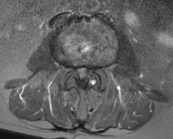

病患B右圖脊椎MRI橫切面腰椎3-4節顯示正常椎管空間。

診斷以病史與神經學檢查 為主。當臨床懷疑神經受壓、症狀持續或需規劃介入/手術治療時,醫師常會安排 MRI(磁振造影) 或必要時的 CT,以確定壓迫的節段、程度與合併病變(例如椎間盤突出或滑脫)。